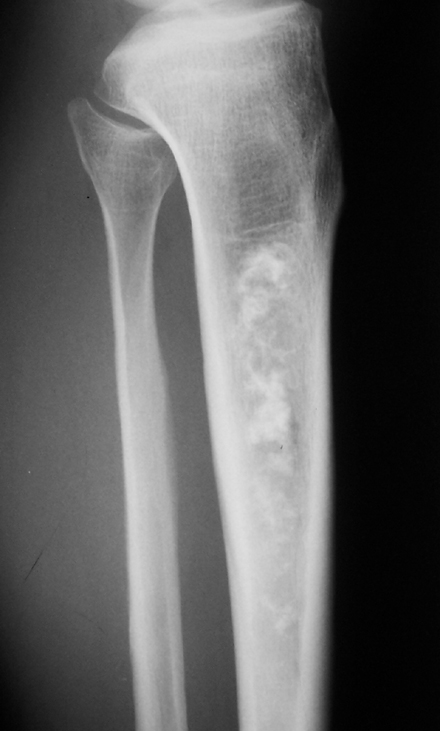

胫骨上段可见斑片状高密度影,密度不均,边界欠清,邻近骨质无破坏,无骨膜反应,周围软组织无肿胀。

多考虑骨梗死可能性大。

胫骨中上段髓腔内可见斑片状钙化,边界较清楚,未见骨膜反应及软组织肿块影。

诊断:胫骨骨梗死。

x线表现:圆形、椭圆形、片状或不规则形密度增高影,其周边可见若干粗细不等、相互连接或交叉的蜿蜒走行的更高密度影。当骨坏死组织被清除吸收、但尚未新骨形成时,则表现为囊状或分叶状透亮区。sehing 等曾将骨梗死的x线表现分4 型:即带条状、辫状、气泡状、多囊状,典型者表现为地图样钙化。

右胫骨中段髓腔内见斑片状密度增高影,边缘清楚,密度不均,未见骨质破坏,无膨胀变形,周围无软组织肿块,考虑骨梗死。

胫骨上段可见斑片状高密度影,边界清楚,无骨质破坏,无软组织改变,应考虑骨梗死。

多考虑骨梗死可能性大。建议mr进一步检查,腓骨中段线样低密度影是骨折线还是伪影?

胫骨髓腔内多发形态不规则钙化/骨化影,呈蚓状分布,周围可见透亮带,骨质无破坏,无骨膜反应,无软组织块影,考虑骨梗死,鉴别诊断要和内生软骨瘤,骨斑点症等区分。